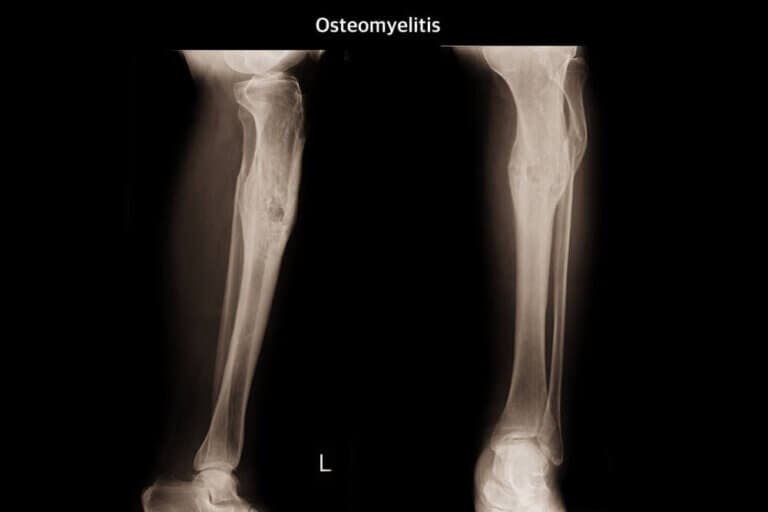

- Radiografía del hueso: se trata de una prueba de imagen para examinar los huesos.